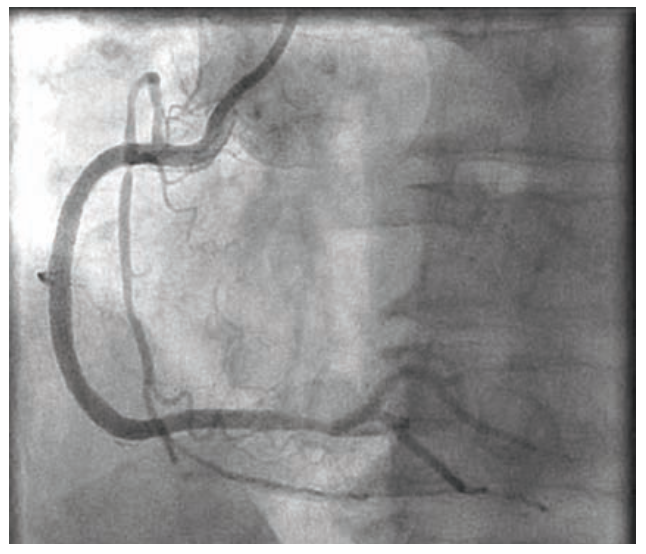

A new Amplatz Left 1 6 Fr guiding catheter was used to place a BMW .014-inch Universal wire (Abbott Vascular) into the mid-distal RCA. A 3.0 mm x 38 mm Onyx Resolute stent (Medtronic) was placed and dilated to 12 atm for 30 seconds. Overlapping proximally, a second 3.5 mm x 38 mm Onyx Resolute stent was dilated to 14 atm for 30 seconds. Using the stent deployment balloon, the overlap zone was dilated to 12 atm for 10 seconds. A Choice PT Floppy wire was placed into the marginal side branch to make sure the branch was safeguarded, and a third 3.5 mm x 38 mm Resolute Onyx stent was placed proximally, dilated to 14 atm for 30 seconds. We then dilated the overlap zone and obtained final angiographic images, which demonstrated a good result (Figure 7).